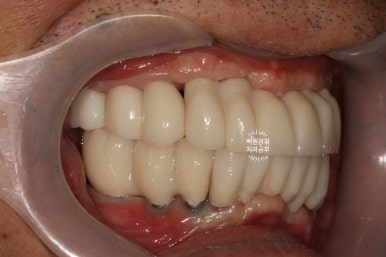

그리하여 완성된 최종보철물입니다!!

옛날부터 임플란트 틀니용으로 사용하시던 임플란트 3개는 임플란트 주위염이 조금 있어 약~간 쇠기둥 색깔이 보인다는 단점이 있긴 하지만, 다른 임플란트들은 꽤나 예쁘게 제작이 되었네요.

위 아래 교합면 사진을 보시면, 과연 이게 임플란트인가? 싶으실거에요. 치아에 지르코니아 크라운을 붙인 것과 큰 차이를 못느낄 정도로 정말 자기 치아같이 예쁘게 제작된 임플란트 크라운을 보실 수 있습니다!!